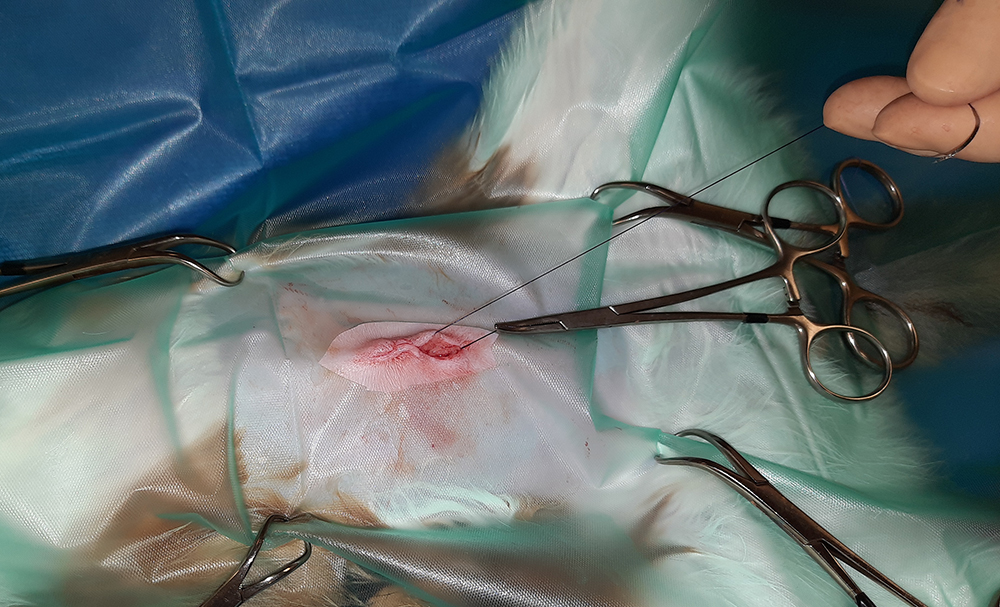

Er wordt een kleine snede gemaakt in de buik, ter hoogte van de navel. Vervolgens worden na elkaar de twee ovaria (=eierstokken) opgezocht, de aanvoerende bloedvaten afgebonden en de eierstokken verwijderd. Hierna wordt de buik in 3 lagen gesloten; de spierlaag, de onderhuid en de huid. Deze laatste wordt onderhuids gesloten met soms een enkele uitwendige knoophechting, zodat er zo min mogelijk hechtingen zichtbaar zijn. Er wordt een wondpleister geplaatst, nadat het wondgebied voorzichtig is schoongemaakt.